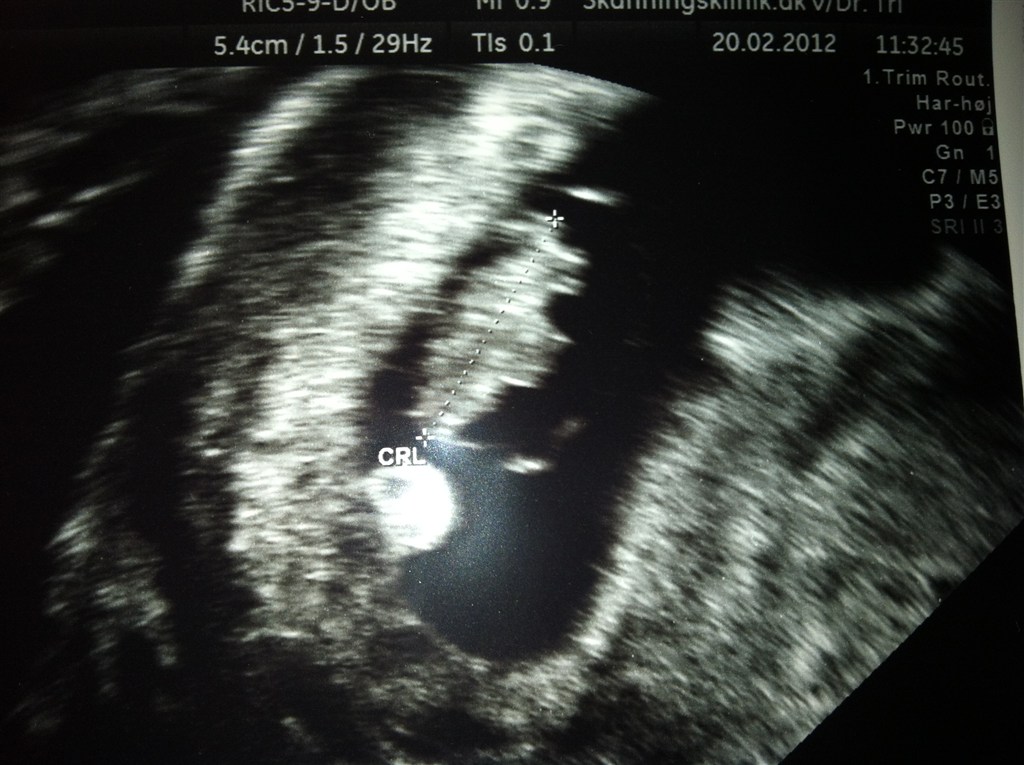

Ja i går var jeg jo til 2. tryghedsscanning og frygtede hvad jeg ville se.... Er i dag 8+0 og det var på dette tidspunkt jeg mistede sidst..

Der var heldigvis et fint hjerte og den lille spir var vokset så fint:-) Var bare så glad...

I får lige et billed med... Her er jeg så 7+6